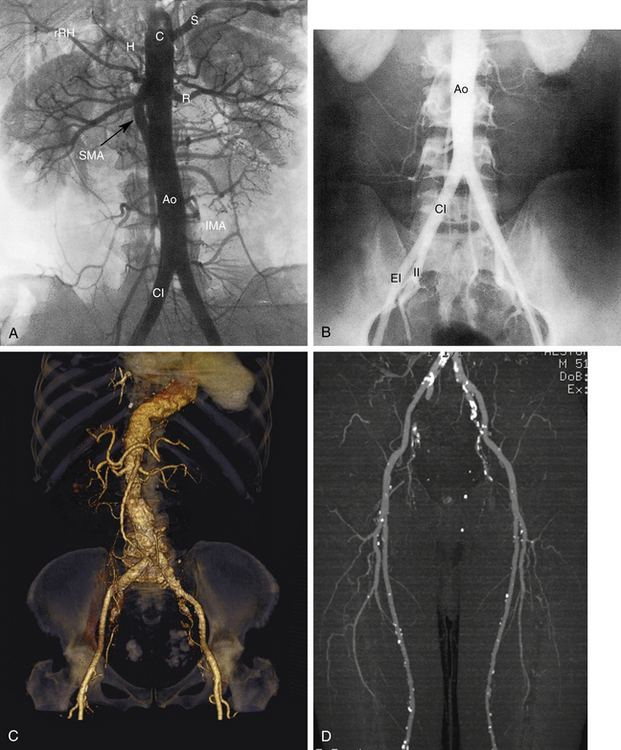

РИСУНОК 13-9. А. Брюшная аорта (Ао) заканчивается разветвлением на общие подвздошные артерии (CI) на уровне позвонка L4. Б. Общие подвздошные артерии делятся в пояснично-крестцовом соединении на внутреннюю (II) и наружную подвздошную (EI) артерии. Внутренняя подвздошная артерия (также называемая подчревной артерией) снабжает внутренние органы и мускулатуру таза. Ветви этой артерии становятся важными сопутствующими путями, как видно на других рисунках. Наружная подвздошная артерия переходит в общую бедренную артерию у паховой связки, как показано на рисунке 13-10 . C : Трехмерная объемная (VR) компьютерная томографическая (КТ) ангиограмма аорты и сегмента подвздошно-бедренной артерии. D. Проекция максимальной интенсивности (MIP) КТ-ангиограммы подвздошно-бедренных сегментов демонстрирует очаговые кальцификации в открытых сосудах. E — магнитно-резонансная ангиограмма (МРА) с усилением гадолинием аорты, подвздошного и бедренного сегментов. Анатомия наглядно иллюстрируется методами трехмерной реконструкции. С, чревная артерия; H, печеночная артерия; НМА, нижняя брыжеечная артерия; R, левая почечная артерия; рРГ – замена правой печеночной артерии; S, селезеночная артерия; СМА, верхняя брыжеечная артерия.